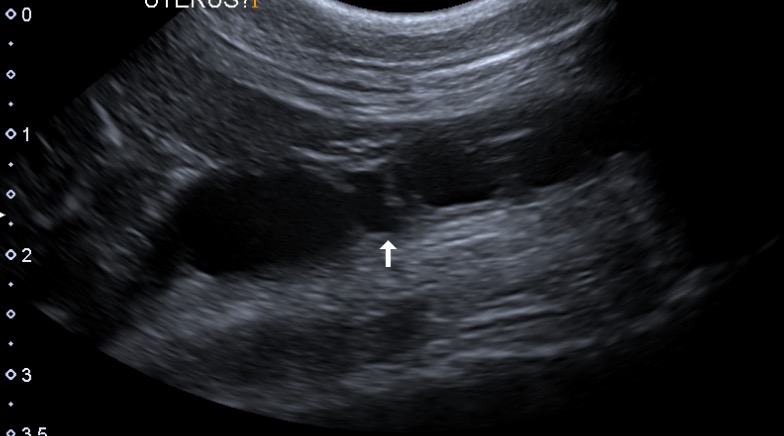

腹部超音波検査では、膀胱の前方に何か液体の貯留しているような部分を認めました。(写真3)

避妊手術をしていないこともあり、子宮内に液体が貯留している可能性が考えられました。

写真3